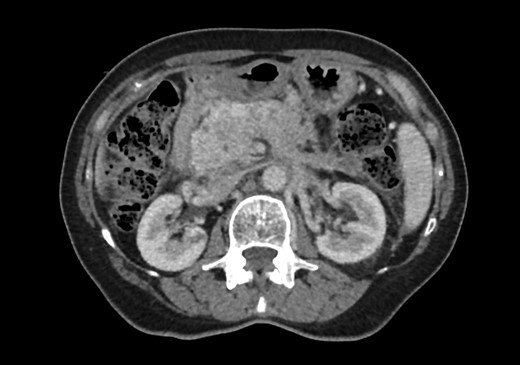

When she now presented with generalized abdominal pain, a CT scan of the abdomen was performed, revealing a lesion in the head of the pancreas measuring 7 × 4 cm2. This mass extended into the porta hepatis and towards the left lobe of the liver, opacification of the splenic vein and superior mesenteric veins was absent, and the confluence of the portal vein could also not be visualized (Fig. 1). Total bilirubin was 13 μmol/L (normal <20), raised ALT at 127 U/L (normal <34) and AST at 69 U/L (normal <31). ALP and GGT were also mildly raised at 135 U/L for ALP (normal 30–110) and 219 U/L for GGT (normal <38). Carcinoembryonic antigen and CA19.9, both markers of pancreatic cancer, were not raised. She was referred to a hepatobiliary surgeon for consideration of a pancreaticoduodenectomy, with the assumption of a primary pancreatic lesion. Due to suspected vascular involvement and potential peritoneal disease seen on the CT, she was regarded as an unsuitable candidate for a pancreaticoduodenectomy. To consider the use of palliative chemotherapy, a percutaneous biopsy for tissue diagnosis was performed. Histology demonstrated a poorly differentiated tumour, surrounded by benign pancreatic tissue with focal areas of perineural invasion by GATA3 positive epithelial cells. These cells also stained positive for ER, K19 and CEA, but negative for PR, B72.3, E-cadherin and HER2. The final diagnosis was poorly differentiated lobular breast carcinoma. Unfortunately, we were unable to compare the expression profiles between the pathology from the axillary dissection and the metastatic disease (Figs 2–4).

Axial slice of portal-venous phase CT scan demonstrating lesion in the head of pancreas.